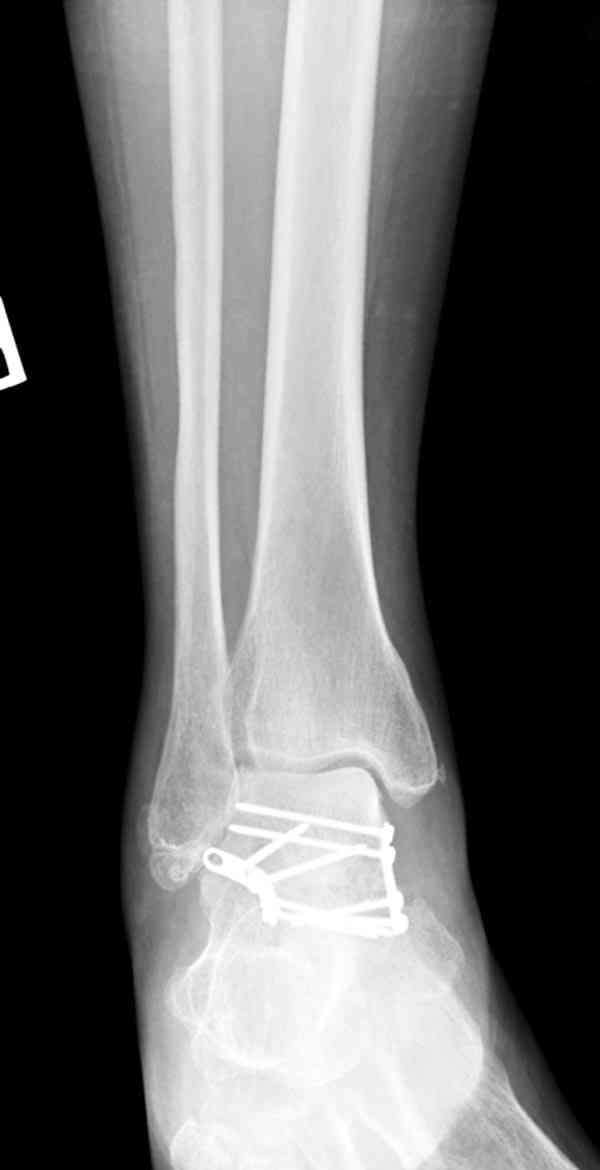

Interesting case

The ankle joint looks ruined. I wonder howcome is it as ruined after 2 days. I would open the joint( Some people would artroscope it) and judge the osteosynthes vs ankle fusion according to the ankle joint condition. The subtalar does not look injured, but if you feel there is a clinical

problem- CT it. Above all- when I see such an X-Ray I call the resident who ordered it and tell him that I would expect him first thing to reduce it on arrival since the soft tissue suffer and I hope that currently the p-nt is reduced to some extent at least.

Sorry- I revised it and the talus is fractured- take him to the theater at once and reduse it with Int Fix

The soft tissue will be a problem- Ex Fix will be better thn plaster

а основании двух видов ренгенограмм невозможно радикально решить о необходимости открытой репозиции или первичного артродеза.

Для оценки состояния нужны дополнительные исследования, например Canale или Broden ренгенограммы и Компьютерная томография.

При переломах тарана всегда имеется риск AVN, а классификация Hawkins поможет разобраться с предполагаемыми осложнениями.

Если в первом типе, когда перелом шейки без смещения, тогда AVN менее 10%, при втором типе когда имеется смещение и вывих тарана в субталарном сочленении меньше 40%, а при типе III когда смещение в голеностопном и субталарном суставах - около 90% и в типе IV, когда происходит полный вывих, риск AVN достигает 100%.

Для оценки состояния нужны дополнительные исследования, например

повторили рентгенограммы и доделали проекции, к единому мнению все еще не пришли